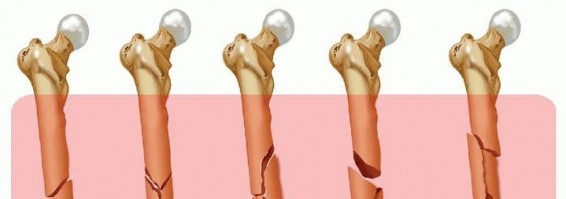

Nail lengths are often determined intraoperatively but can be ascertained by imaging the contralateral femur. Radiographs are evaluated to determine the location and morphology of the fracture; they should be scrutinized for nondisplaced secondary fracture lines that could become displaced during operative treatment. Occasionally, fracture fragments may be stuck in the canal and may need to be pulled out. In the case of fractures that show significant shortening preoperatively, it may be difficult to restore length off the fracture table. A trial reduction should be performed under fluoroscopy before the start of the procedure; the patient must be paralyzed for the procedure. If length is difficult to restore manually, then a femoral distractor should be used for the procedure. Placement of the femoral distractor is described in the section on Fracture Reduction. Before preparing and draping the injured limb, the surgeon should examine the contralateral extremity to determine the patient's normal leg length and rotation. Femoral length can be evaluated by using a radiographic ruler and intraoperative fluoroscopy ( FIG 7A). Normal rotation can be determined by flexing the hip and knee and checking the patient's normal internal and external rotation of the hip and by examining the normal resting position of the foot as the patient lies supine on the operating room table ( FIG 7B).  ---

---  ### FIG 7 • A. Schematic lateral view of a patient on a radiolucent operating room table, depicting how to use a radiopaque ruler and fluoroscopy to determine femoral length. B. Schematic anterior view of a patient on the operating room with the uninjured hip and knee flexed, checking the patient's normal internal and external rotation of the hip.

### FIG 7 • A. Schematic lateral view of a patient on a radiolucent operating room table, depicting how to use a radiopaque ruler and fluoroscopy to determine femoral length. B. Schematic anterior view of a patient on the operating room with the uninjured hip and knee flexed, checking the patient's normal internal and external rotation of the hip.